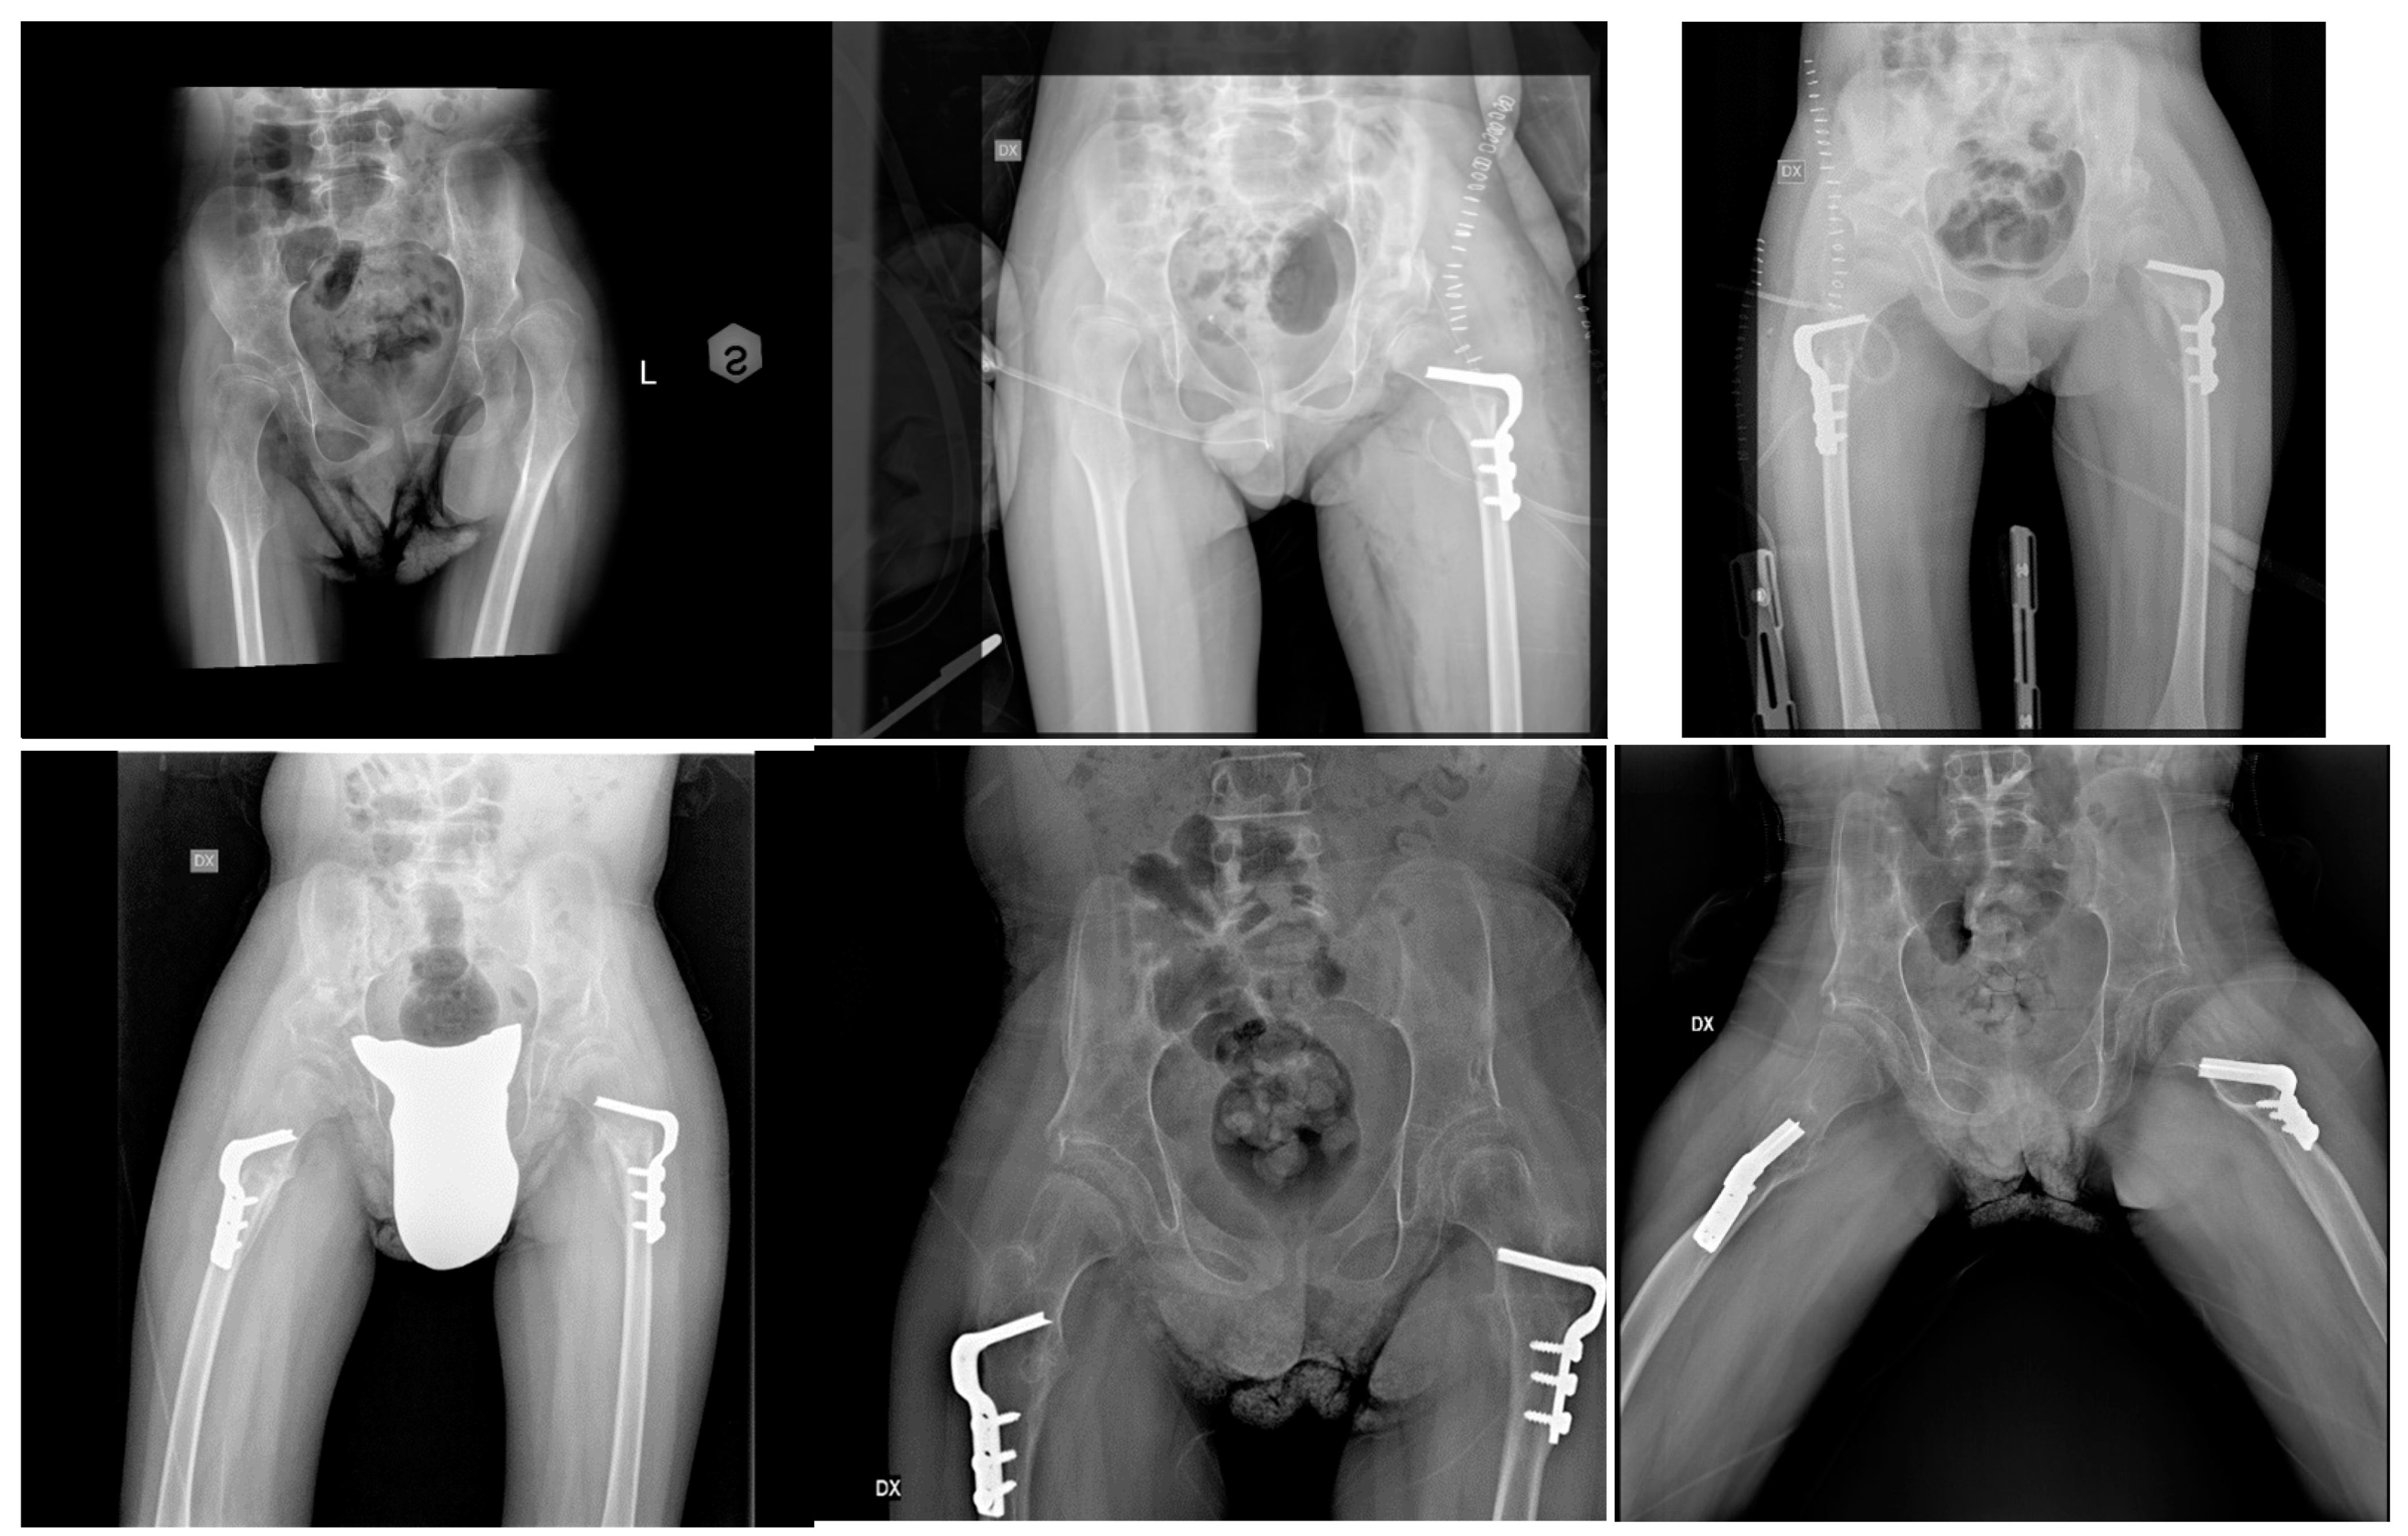

Radiographic and Clinical Results of Combined Bone and Soft-Tissue Tailored Surgeries for Hip Dislocation and Subluxation in Cerebral Palsy

2. Materials and Methods

3. Results

3.1. Acetabular Index (AI)

3.2. Reimer’s Index (RI)

3.3. Neck–Shaft Angle (NSA)

3.4. Complications

- blood transfusion in 1 case (1.1%);

- wound dehiscence in 1 case (1.1%).

- hip dislocation in 6 cases (6.9%), requiring new surgery (in 84 days);

- graft resorption in 3 cases (3.4%), requiring new surgery (in 6 days) only in one case;

- infection in 1 case (1.1%), requiring removal of metal;

- hardware failure required re-surgery (in 2 days) in one case (1.1%);

- uncontrolled pain for more than 6 months from surgery in one case (1.1%), with complete resolution at the latest follow-up.